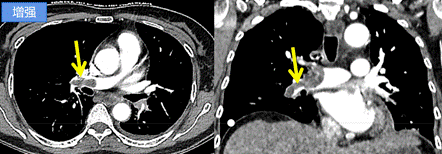

增强CT是在检查前先将含碘的对比剂注射进静脉后再进行扫描,是对平扫CT的补充,由于碘对比剂进入血液后,血液中含碘浓度升高,在病变部位与器官中的碘浓度形成密度差异,这样显影就更加清晰,更有利于对病灶范围、数量及性质等做出判断。因此,增强扫描是对CT平扫的补充,可以理解为CT平扫的升级版。

检测血流和血管状况:增强CT可以更清晰地显示血管的形态和分布情况,发现血管源性病变,比如冠状动脉狭窄、肺动脉栓子、脑血管疾病、动脉瘤、动脉夹层等。

显示病变的边缘和内部结构:有些病变在平扫CT上可能难以清晰地显示其边界和内部构造。增强CT可以使病变的边缘更加清晰,有助于医生准确定位和评估病变的性质。